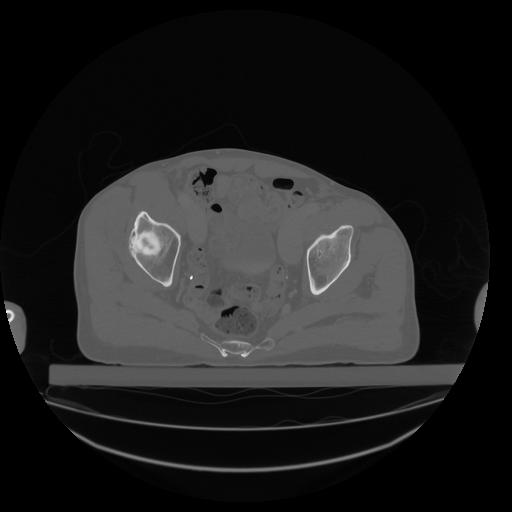

34 CUERPO,CE,Vol,1.0,CUERPO,,